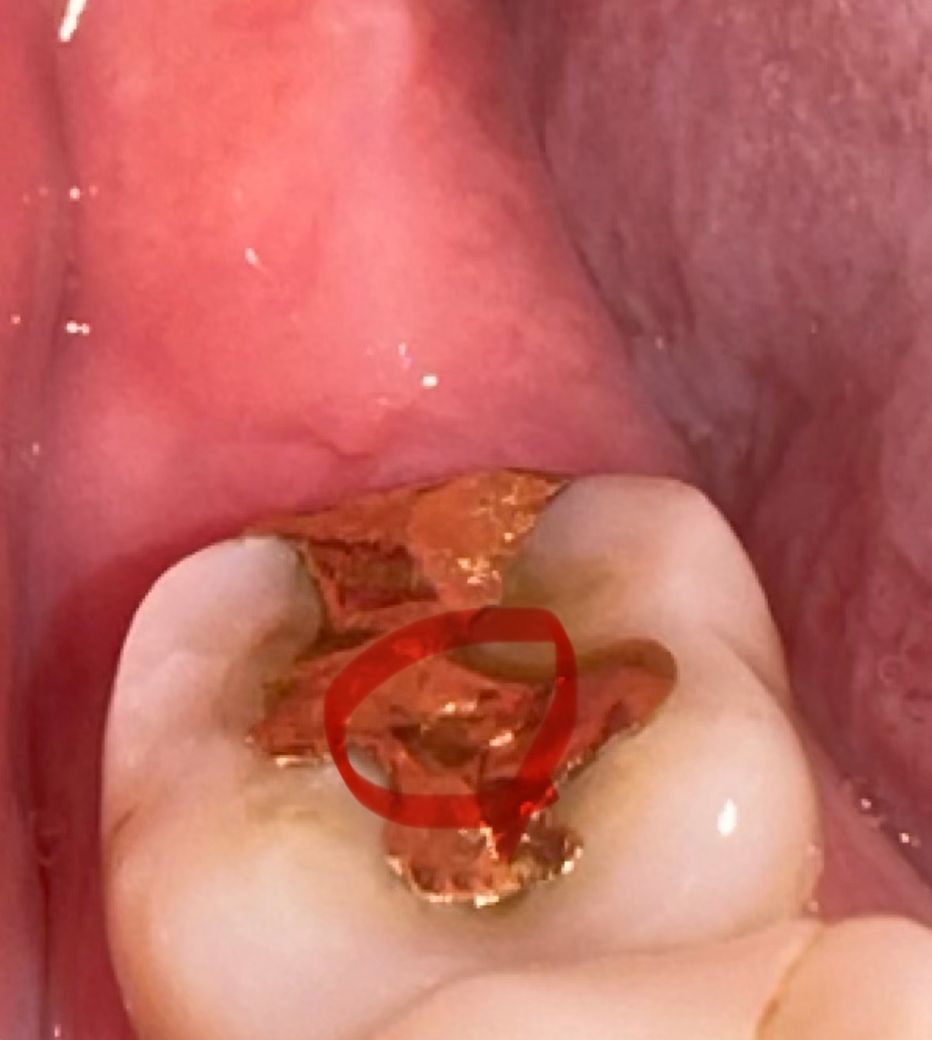

사진이라 표시는 잘 나보이진 않는데 원래는 보철물이 이러지 않았는데 갑자기 동그란 모양으로 파였어요 이쑤시개로 대보니 내려가는것처럼 푹 들어가요 ㅠㅠ 보철물이 닳아서 파일수도있나요? 만약에 닳아서 그런 경우면 교체가 급한거일까요 ㅠㅠ 크게 시리거나 아프거나 통증이 있지는 않습니다 ㅠㅠ

해당 보철물은 금인레이 인데요

금의 경우에는 사용하다보면 마모되거나 파일 수도 있습니다.

자연스럽게 마모가 될 순 있습니다. 별다른 증상이 없다면 보철물을 굳이 교체하진 않아도 괜찮습니다. 다만 사진상 보이기에는 자연스럽다기 보다는 인위적인 홈이 파여진 것 같은데 특별히 위쪽 어금니 치료 사항과 관련해서 관계된 부분인지 치과에 가서 확인해볼 필요도 있겠습니다.